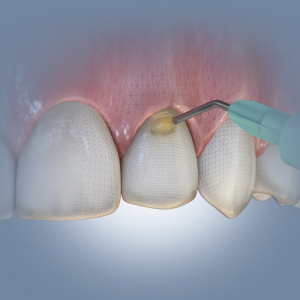

Implantology Updates

This Compendium eBook features a continuing education (CE) article on hard- and soft-tissue augmentation for implant therapy in the esthetic zone. This eBook also includes a case report article on a minimally invasive technique for the reconstruction of class III sockets with simultaneous i...

Digital Imaging Advances

This Compendium eBook offers a continuing education (CE) article on CAD/CAM custom-made titanium meshes to facilitate guided bone regeneration. This article includes two case studies of patients with severe ridge atrophy for whom CBCT and CAD/CAM were used to design titanium meshes for ridg...